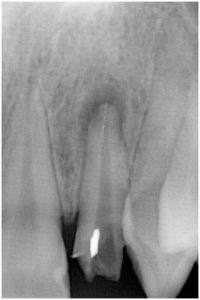

次の写真をご覧ください。これは、去年の8月に来院された患者さんが先日お見えになったため、根の治療を終えたところが治ったかどうか確認した画像です。

1枚目が初診時です。根の先に黒い陰が認められますね。